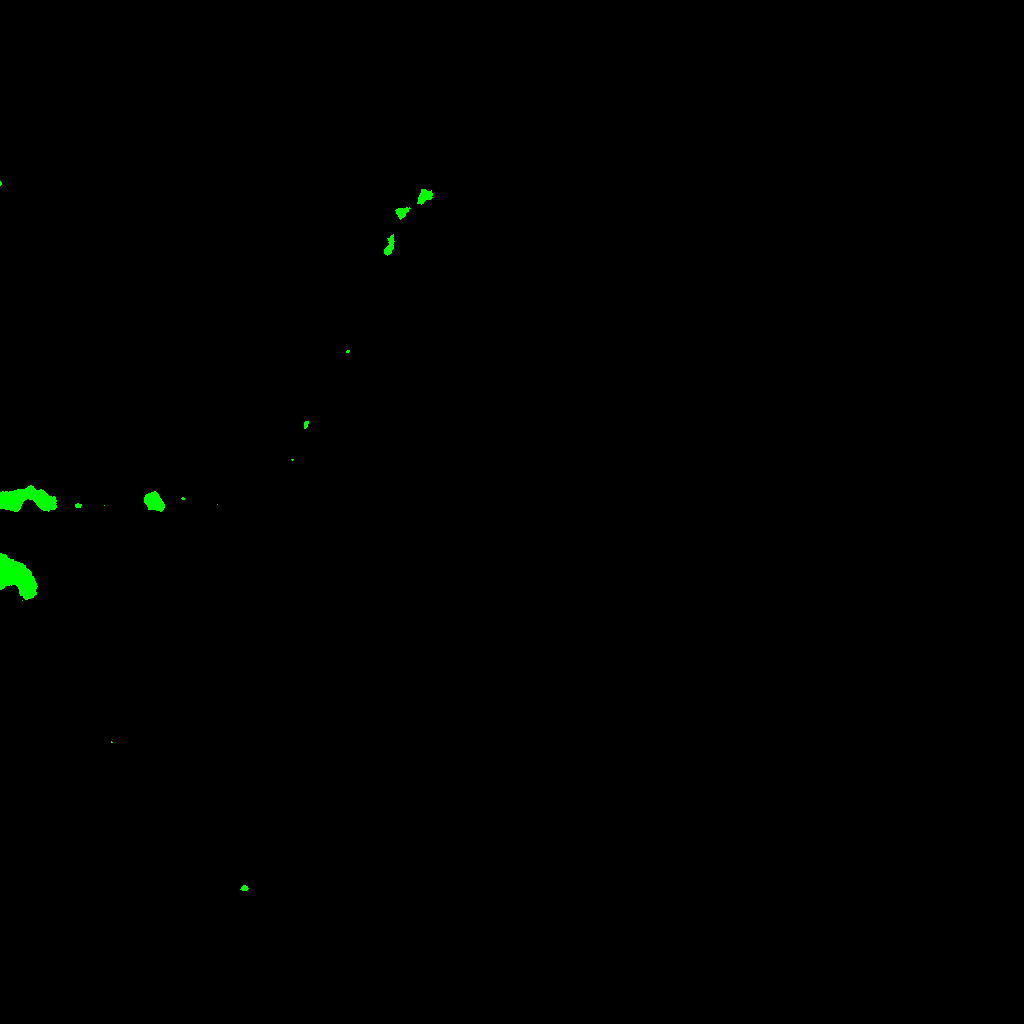

More concretely, we proceed as follows. As we have explained previously, we apply the salt-and-pepper removal step to all the slides of the z-stack, the result of that in our case study can be seen in Figure 2.

Refer to captionRefer to captionRefer to captionRefer to captionRefer to captionRefer to captionRefer to captionRefer to caption

Figure 2: Processed median and Huang’s filter of each z-stack plane from Figure 1 neuron.